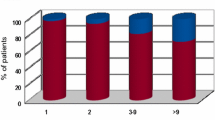

Patients were predominantly male (60.5 %, n = 121) and had a median age of 64.5 years with a range from 32 to 91 years. 47.5 % (n = 95) were older than 65 years. In patients ≤65 years, median age was 57 years (nmale = 56, nfemale = 49), while median age in patients >65 years was 72 years (nmale = 65, nfemale = 30) (Fig. 2a, b). The population comprised patients with non-small-cell lung cancer (NSCLC) (n = 89), small-cell lung cancer (SCLC) (n = 14), breast cancer (BC) (n = 20), malignant melanoma (MM) (n = 30), renal cell carcinoma (RCC) (n = 17), colorectal cancer (CRC) (n = 10) and patients with other tumors (OT) (n = 20). Patients with RCC were significantly older (73 years) than patients with BC (58 years, p = 0.001), MM (61 years, p = 0.009) and NSCLC (63 years, p = 0.005) or other tumors (62.7 years, p = 0.04). 31 of 200 patients (15.5 %) had a singular cerebral metastasis, 42 patients (21 %) had two metastases, 91 patients (45.5 %) 3–9 metastases and 36 patients had >9 metastases.

Patient groups and age-dependency of white matter hyperintensities. a Distribution of patients ≤65 years and older than 65 years. b Distribution of patients according to decades of age. c Patient age and different WML grades. d Correlation plot of patient age and WML grades. Data is displayed in boxplots (Box interquartile range (IQR), horizontal line median, whiskers max 1.5× IQR, N number of patients)

A significant positive correlation between age and WML was identified by Pearson’s Chi square test of Independence (pχ2 = 0.001; r = 0.422). This was confirmed in Kruskallis–Wallis-Test of independent samples. There was a tendency of linear relation between age and grade of WML (Fig. 2).

Influence of WML on mean number (a–c) and diameter (d) of BM. a Mean number of metastases according to WML grade. b Mean number of metastases according to WML grade in patients ≤65 and >65 years. c Mean number of metastases in patients with NSCLC and other tumors than NSCLC according to WML grade. d Mean diameter of metastases in mm according to WML grade. Data is displayed in boxplots (Box interquartile range (IQR), horizontal line median, whiskers max 1.5× IQR, N number of patients)